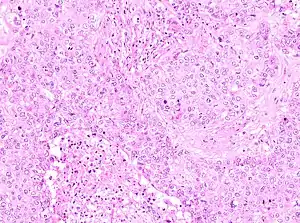

The microscopic histopathology of PACB tumors prepared with hematoxylin and eosin staining shows that >90% of the tumors consist of apocrine gland-like tissue. The lesions must also show that tumor cells have broken through their ducts of origin to invade adjacent tissue in at least one area. Most of the tumor cells (termed type A cells[15]) typically appear somewhat more irregular than normal apocrine gland cells. They have abundant eosinophilic (i.e. pink due to the uptake of the eosin dye) cytoplasm which contain numerous granules[11] and large mitochondria.[15] Their nuclei are large, variably sized and shaped, have multiple nucleoli (which are eosinophilic[11] and may be distinctively large in size[14]), and are surrounded by highly visible nuclear membranes. The cells are arranged into solid sheets, nests, papillae, and/or cords (see Figs. 1 and 2).[11] The tumor cells' cytoplasmic granules test positive when treated with the PAS diastase stain.[16] Binucleated cells, i.e. cells with two nuclei, are common.[10] Less commonly, type B apocrine cells are present; these cells have a more foamy and vacuolated cytoplasm (i.e. containing multiple vacuoles) than type A cells[15] and often resemble foamy histiocytes or sebaceous gland cells.[17] The tumor cells have low to moderate rates of proliferation based on their Ki-67 protein levels.[7] PACB tissues may have localized areas that contain mucin-like secretions within their luminal ducts,[10] localized areas of necrosis (i.e. foci containing dead or dying cells), and/or microcalcifications spotted throughout the apocrine tissue.[11] The stroma (i.e. connective tissue between the sheets, nests, papilla and cords of cells) typically contains non-malignant, infiltrating lymphocytes (see Fig. 3). In an examination of 41 PABC tumors, 33 (80.5%) had <50% of their stroma tissues infiltrated with these cells while 8 (19.5%) had ≥50% of their stroma tissues infiltrated with them. Tumors with ≥50% of their stroma infiltrated with lymphocytes tended to have carcinoma cells that had high rates of proliferation.[11] Metastatic and recurrent PACB tumors have a histopathology similar to their original primary tumors.[14]